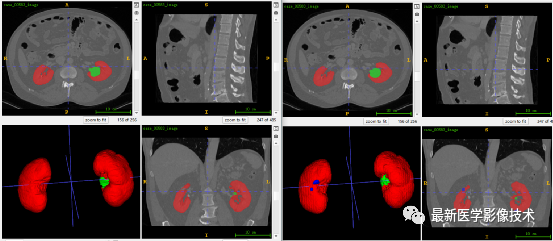

5、验证集分割结果

左图是金标准结果,右图是预测结果。